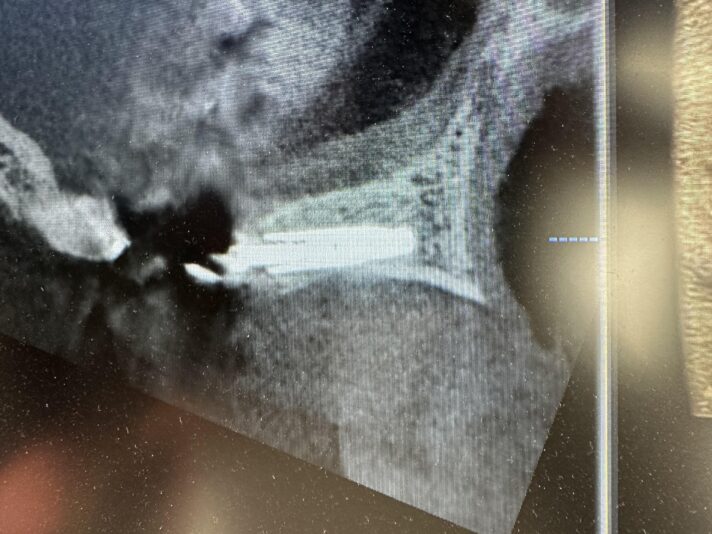

• Looks good, right?!? Not once you see the cbct and create a larger full thickness flap. What would you do here? What are your options? This happened during one of our live surgery courses. Please leave a comment below on what you would do and a couple options we may have. After I recieve several comments I will post a follow up post next week…

Read more

• implant position looks too buccal to me in this photo. i’d remove and start a new osteotomy and sink the implant to the level of the lingual bone

1